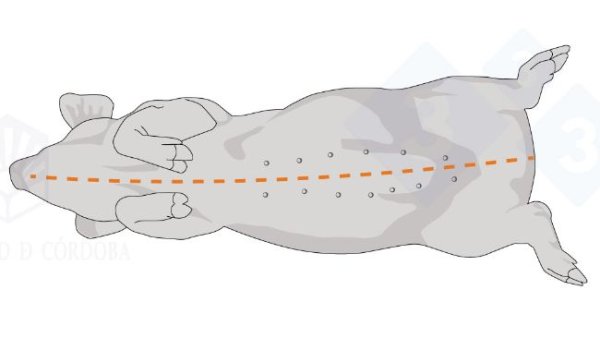

Mientras que en las dos primeras entregas hemos abordado la necropsia en decúbito lateral, en esta tercera entrega explicaremos como hacer la necropsia en decúbito supino.